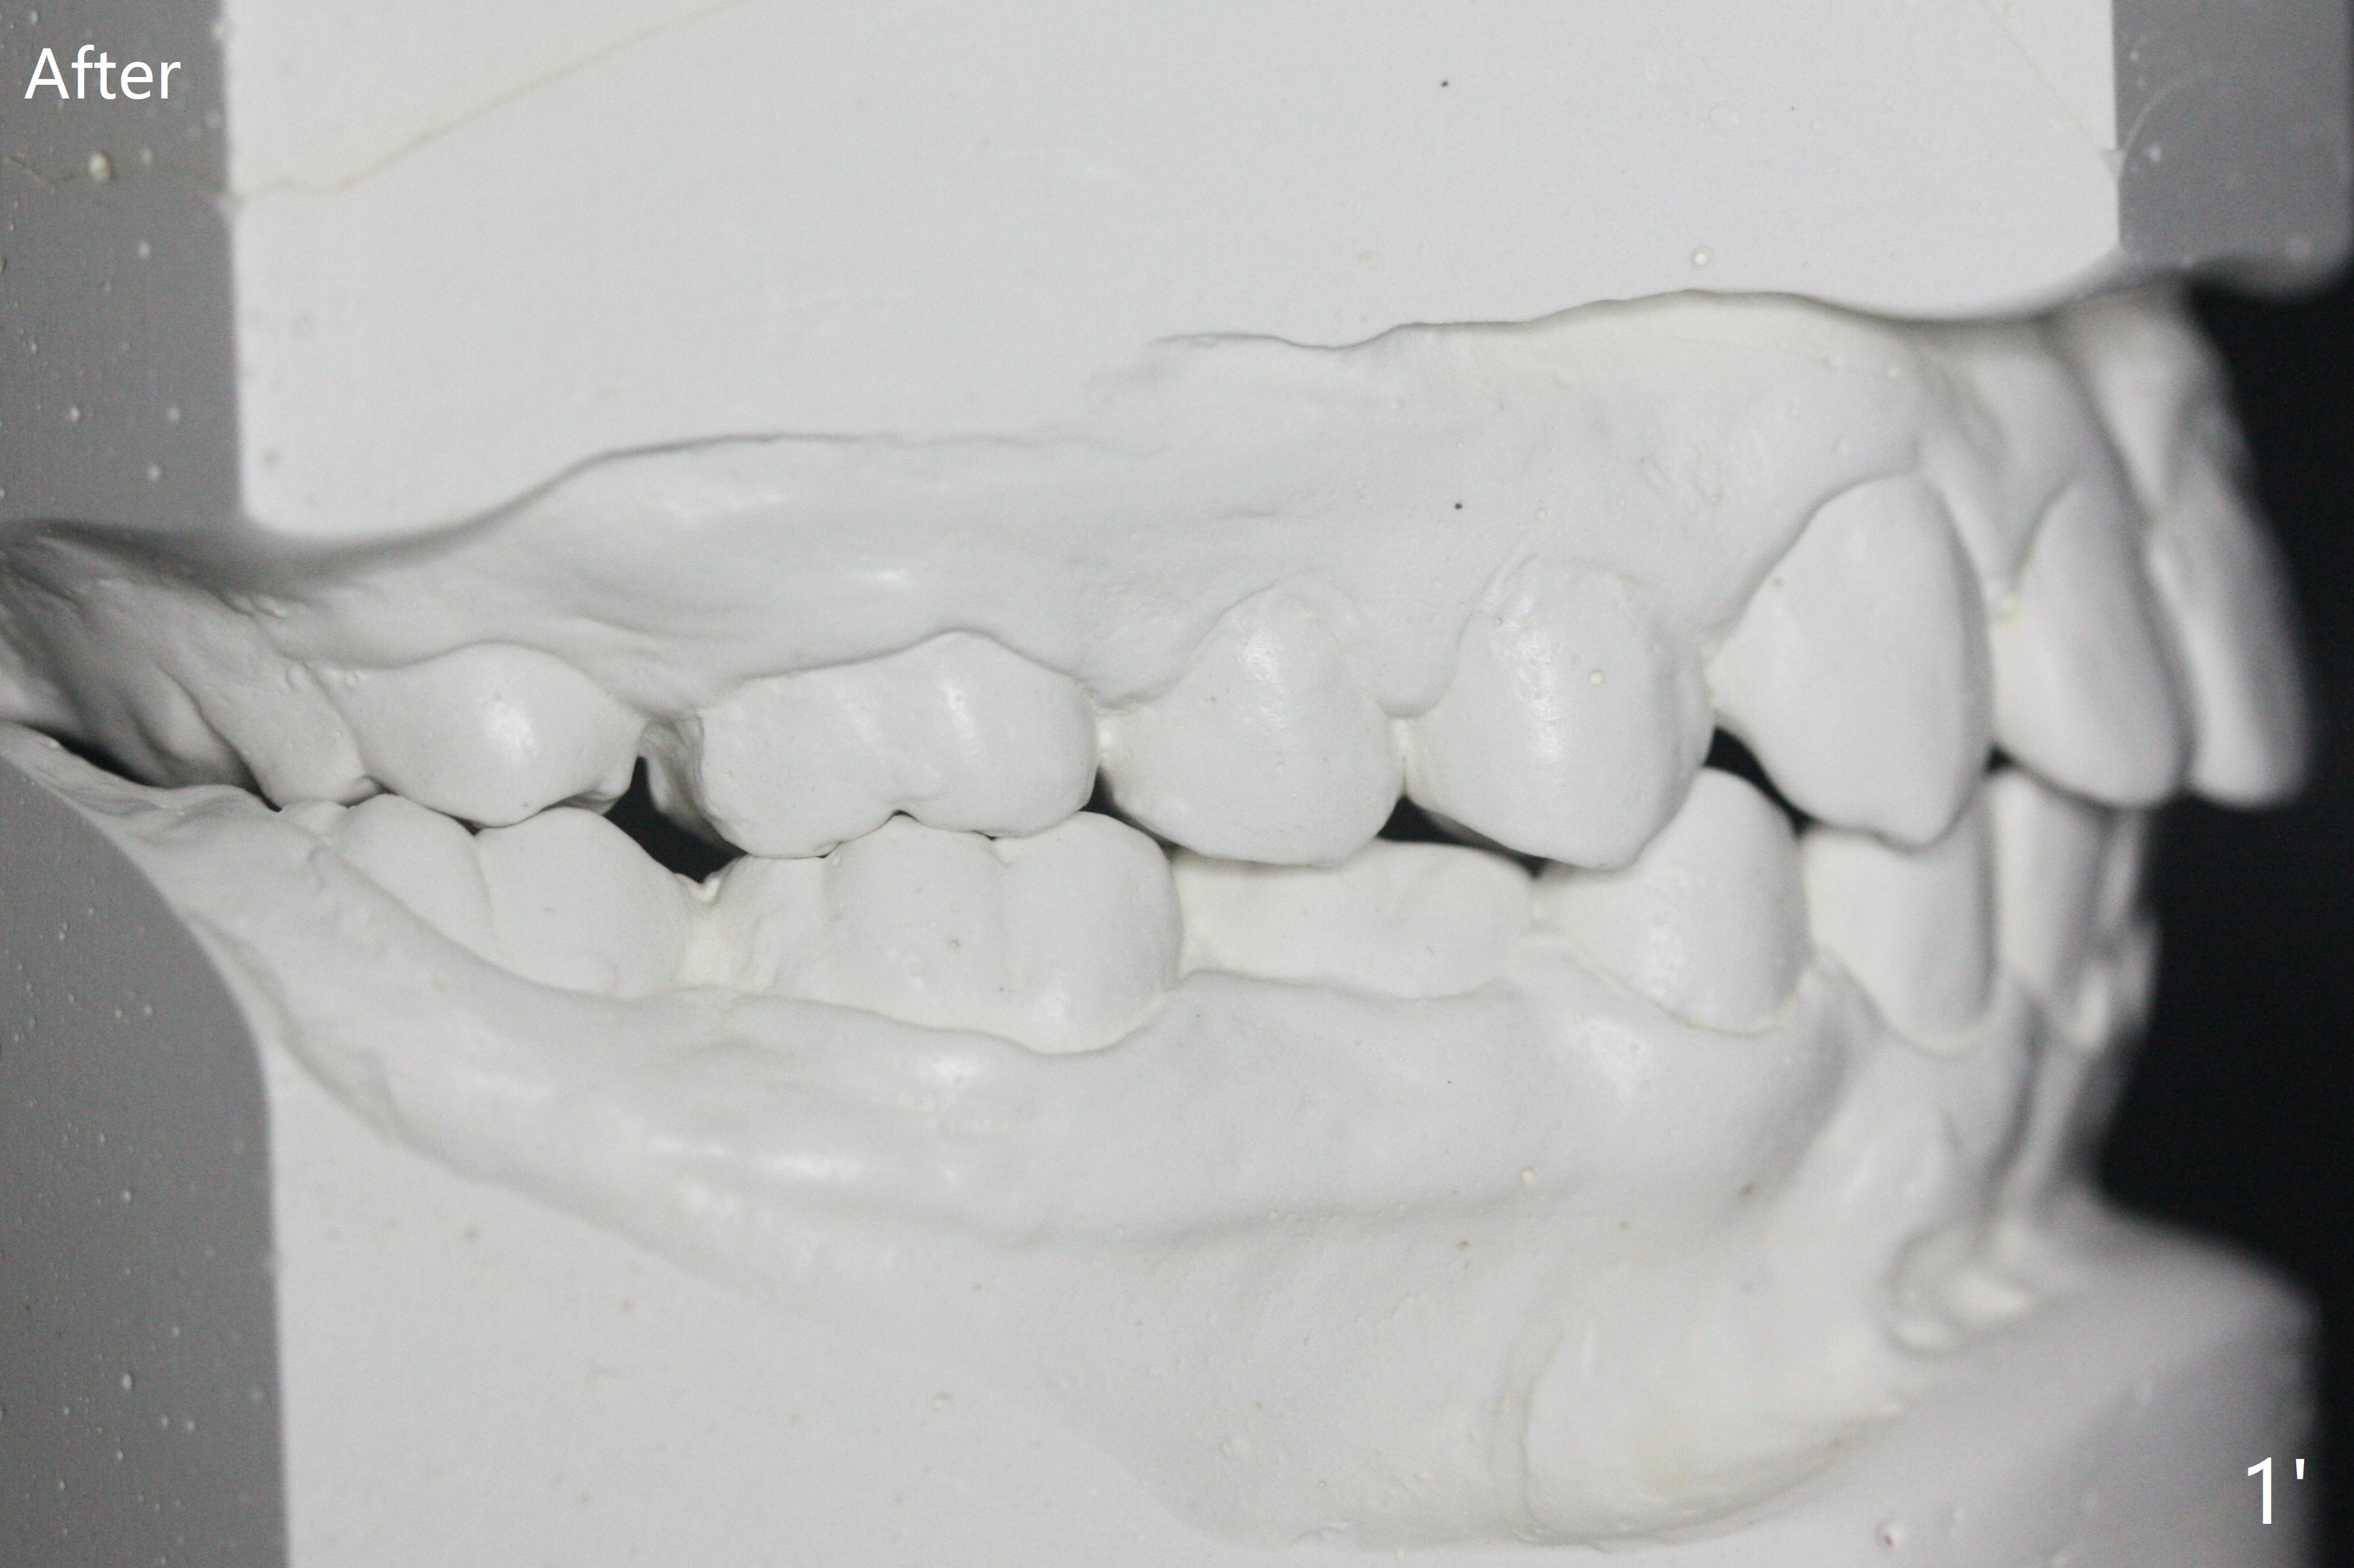

One-year-8-month orthodontic treatment reduces anterior overjet (Fig.1 (double arrows),1', with facial profile improvement), corrects right 1st molar cross bite (Fig.2,2') and dental midlines (Fig.3,3'), closes the diastema between UL3 and 4, extrudes UL5 (Fig.4,5,4',5'), and increases space for future implant at LL4 (Fig.6,6'). In fact large arches with distemata make the treatment possible! Extrusion of UL5 leads to root development (Fig.7, 7' (R)). The increased space at LL4 (Fig.7' *) appears insufficient for an implant.